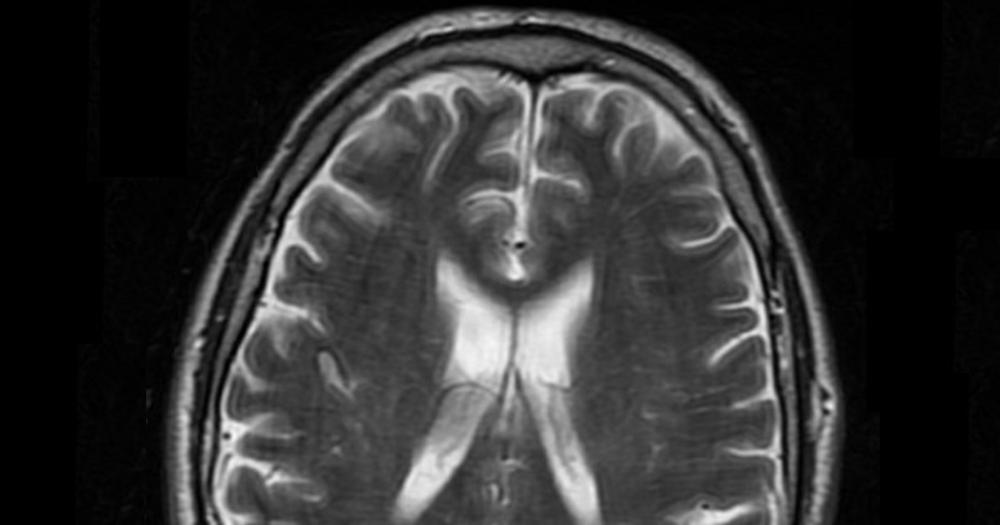

The wiring network in the brain was not better preserved in the Generation 100 groups that were offered organized exercise, compared with the participants who were advised to exercise on their own. Nevertheless, the results suggest that high fitness and high-intensity training are beneficial for maintaining better structure in this network.

Good signaling in the brain depends on intact nerve fibers and a thick layer of myelin that insulates these fibers. Together, nerve fibers and myelin form the white matter of the brain. In this study, we used MRI to examine the structural organization of white matter in 105 of the 70-77 year old participants in the Generation 100 project. The measurements were made at start-up and after one, three and five years of exercise follow-up, respectively.

We found no beneficial effect of high fitness or long-term organized exercise on the development of white spots in the brain of older adults. These spots can be seen on MRI, and are common after the age of 50. The spots are scars in the wiring in the brain, and are associated with impaired gait function, cognitive impairment, depression and stroke. Neither in the participants who were offered organized interval training with high intensity, nor in those who could attend moderate training sessions, did the growth of these scars develop differently than in those who exercised on their own.

The study includes 105 of the participants in the Generation 100 study. Their brains were checked with MRI before, during and after the five-year exercise period. The extent of white spots increased in all three groups, especially during the last couple of years of the 5-year period. The other three studies we have published on brain health in the Generation 100 study show that high fitness protects against cognitive impairments. However, we found no association between fitness and the development of white spots. Nor did those who improved their fitness during the study have slower development of white spots in the brain than the rest of the participants.

Organized exercise follow-up did not prevent loss of brain cells compared to giving general exercise advice without offering organized exercise sessions. However, Generation 100 participants with high cardiorespiratory fitness at the onset of the study had thicker cerebral cortex throughout the five-year exercise period than those who were less fit.

To check for changes in brain volume and the thickness of the cerebral cortex, we performed MRI scans of the brains of 105 of the 70-77 year old participants in the Generation 100 study both before, during and after the exercise intervention. The group that exercised on their own without organized follow-up had less than age-expected atrophy of the hippocampus and the foremost part of the brainstem. In the groups exercising at high and moderate-intensity, respectively, the atrophy was somewhat greater than among those who exercised on their own, but still not higher than what is expected for people in their 70s.